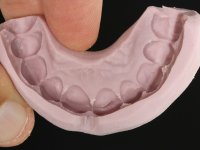

Realizado o diagnóstico e tomada a decisão quanto ao tratamento a executar, tornou-se importante definir qual a sequência de trabalho a adotar no sentido de conseguir a reabilitação da D.V.O. (V.D.O), de forma progressiva e equilibrada. Na primeira fase fez-se uma pré-impressão da arcada inferior com silicone tipo “putty” e em seguida realizou-se o preparo dentário de todo o sector posterior. O preparo para os overlays foi feito coronalmente à linha amelo cementaria no sentido de ser o mais conservador possível. A impressão foi feita com técnica de dupla mistura após afastamento gengival realizado com pasta de caulino. A provisória foi realizada com resina composta de polimerização dual. Em laboratório foram realizados os overlays após se ter aberto ligeiramente (1,5mm) a D.V.O. nos modelos montados em articulador semi-ajustável. Simultaneamente o sector antero-inferior foi encerado no sentido de acompanhar este aumento da D.V.O. Também foi confecionada uma chave de silicone translucido para posterior confeção dos provisórios antero-inferiores. Em boca foi primeiro realizada a provisionalização dos dentes anteriores utilizando resina composta previamente aquecida após preparação das superfícies dentárias para a adesão. Foi colocado o dique de borracha para promover o isolamento absoluto e posteriormente foram colados os overlays. Em laboratório foi realizada nova chave de silicone para confecionar os provisórios antero-superiores. Seguidamente em boca foram preparados os seis dentes antero-superiores após colocação do fio de afastamento gengival. Feita a preparação adequada das superfícies dentárias foi realizada a impressão com técnica de dupla mistura e a respetiva provisória. Em laboratório foram confecionadas 6 facetas feldespáticas num modelo de trabalho tipo “Geller”. A provisória foi removida e as facetas foram coladas em boca utilizando um isolamento relativo competente. Esta opção foi tomada em virtude de uma prévia experiencia negativa com a colocação do dique de borracha na mandibula. Após a colagem dos laminados antero-superiores foram dadas 12 semanas para avaliar a adaptação do paciente à nova situação e então iniciar a confeção das facetas antero-inferiores. Após colocação do fio de afastamento gengival. foram feitos os preparos dentários adequados e em seguida foi feita a impressão. Também foi feita a preparação do dente 3.4 que, entretanto, tinha sofrido uma fratura do overlay. As facetas e a restauração do 3.4 foram realizadas num modelo de trabalho tipo “Geller”. Após remoção da provisória, as facetas foram coladas em boca, utilizando um isolamento relativo pelas razões apontadas anteriormente. Após colocação do trabalho o paciente foi reabilitado por outros colegas com um implante na zona do 2.6 e substituição da coroa aparafusada sobre o implante colocado no local do 3.5. Posteriormente surgiram fraturas nos overlays dos dentes 4.7 e 3.7 que foram reabilitados com overlays em Zr.